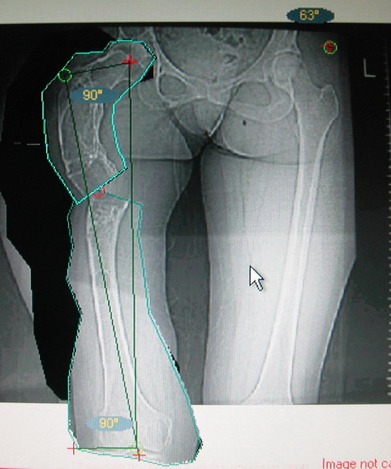

Возможна аппаратная коррекция оси с формированием клиновидного регенерата, которая решила бы и проблему укорочения (что, впрочем, нужно уточнить по схеме, сделанной по рентгенограмме с хорошим захватом смежных суставов - схемка по присланному снимку в приложении). По окончании коррекции - блокируемый стержень, который и сократит время пребывания в аппарате, и вообще возврата к нормальной жизни, а также будет мерой профилактики патологических переломов.

А может быть, если при планировании выяснится, что "открытый клин" решает все проблемы, и есть достаточное приведение в тазобедренном суставе, пойти на одномоментную операцию - чрескожная поперечная остеотомия на вершине деформации и закрытый интрамедуллярный остеосинтез.

Собственно сустав не беспокоит, объем движений полный. По скиаграммам получается, что достаточно одной остеотомии на вершине деформации, чтобы восстановить длину и вывести коленный сустав в нужное положение.

Т.к. укорочение 7 см, то начинать будем с соеотомии и коррекции аппаратом. Спасибо

Моё мнение, что двойная остеотомия бедра с аппаратом Илизарова + Гексаподный механизм, или Тэйлора, В данной ситуации является методом выбора. Я очень извеняюсь за качество прилагаемых снимков, в которых я постарался отразить разницу междe одной и двумя остеотомиями бедра.